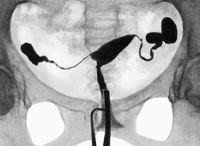

С помощью УЗИ органов малого таза определяется строение половых органов, наличие у пациентки регулярной овуляции, признаков возможного воспаления, спаек, гидросальпинкса, новообразований. На ЭхоГСГ при полной непроходимости маточных труб можно увидеть растяжение стенок матки и расширение ее полости введенным стерильным физраствором; при частичной форме и спаечном процессе данные не показательны. На контрастных рентгенограммах маточных труб, полученных в ходе ГСГ, по форме просвета определяют факт и степень непроходимости каждого отдела труб и локализацию преграды (без уточнения ее характера).